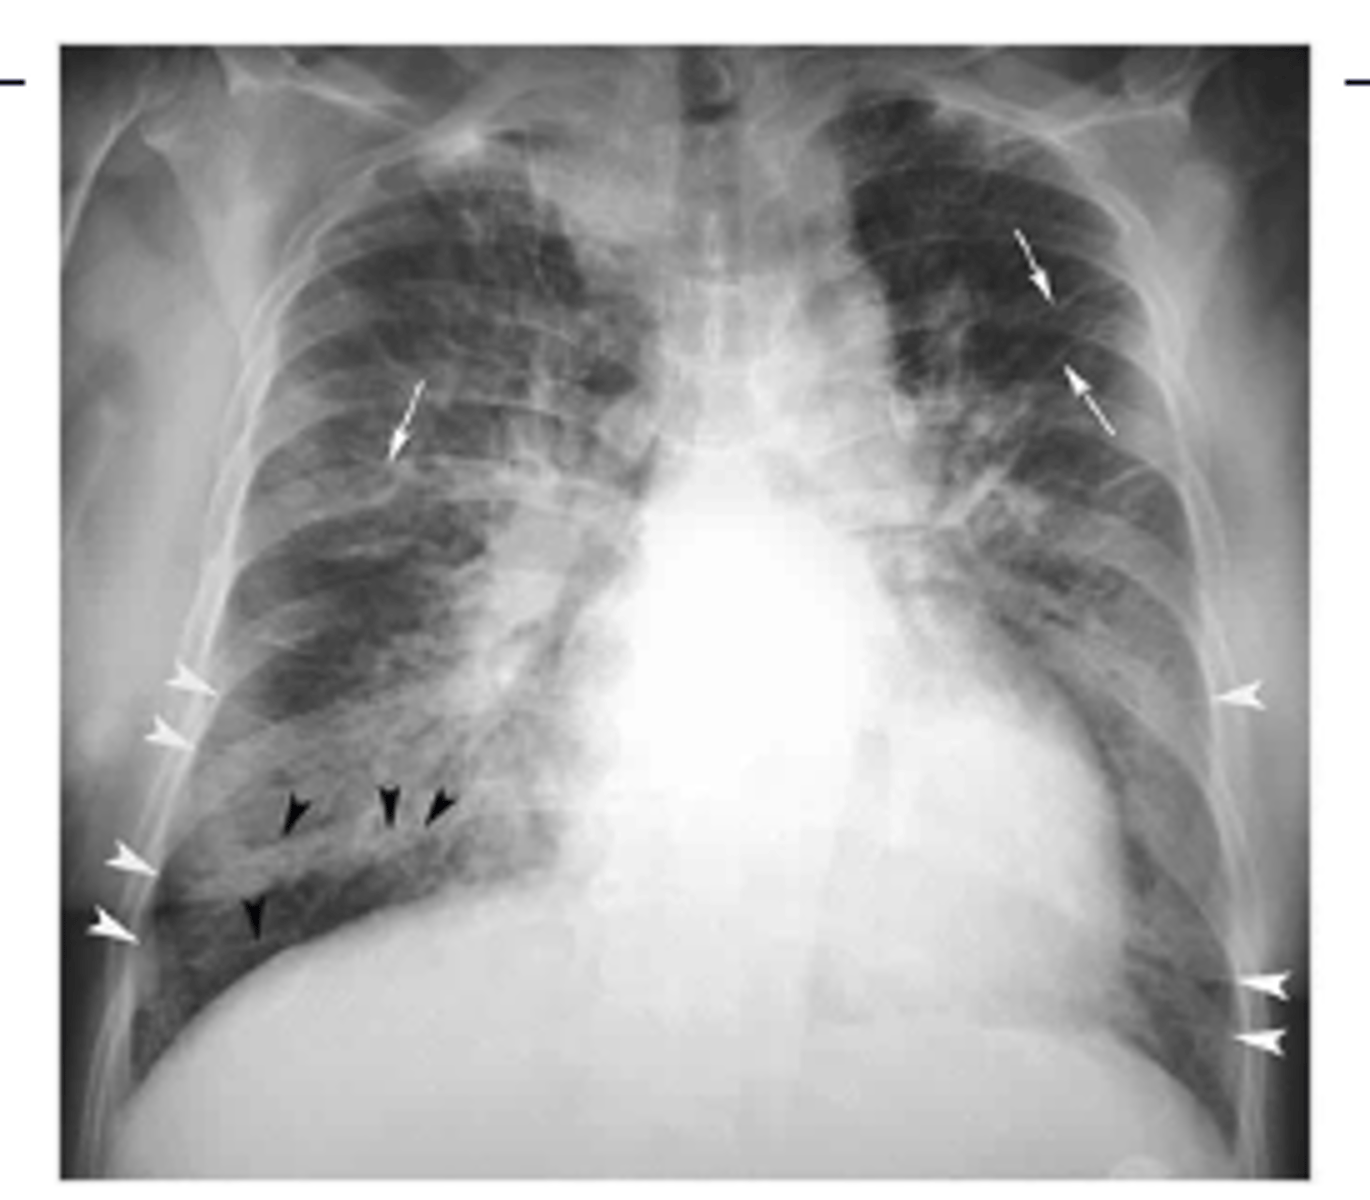

Common x-ray finding of military TB. What makes military TB particularly deadly?

diffuse bilateral infiltrates with very small nodules

-late phase of TB: potentially fatal form of the disseminated disease due to the hematogenous spread of tubercle bacilli to the lungs, and other organs.

<p>diffuse bilateral infiltrates with very small nodules</p><p>-late phase of TB: potentially fatal form of the disseminated disease due to the hematogenous spread of tubercle bacilli to the lungs, and other organs.</p>